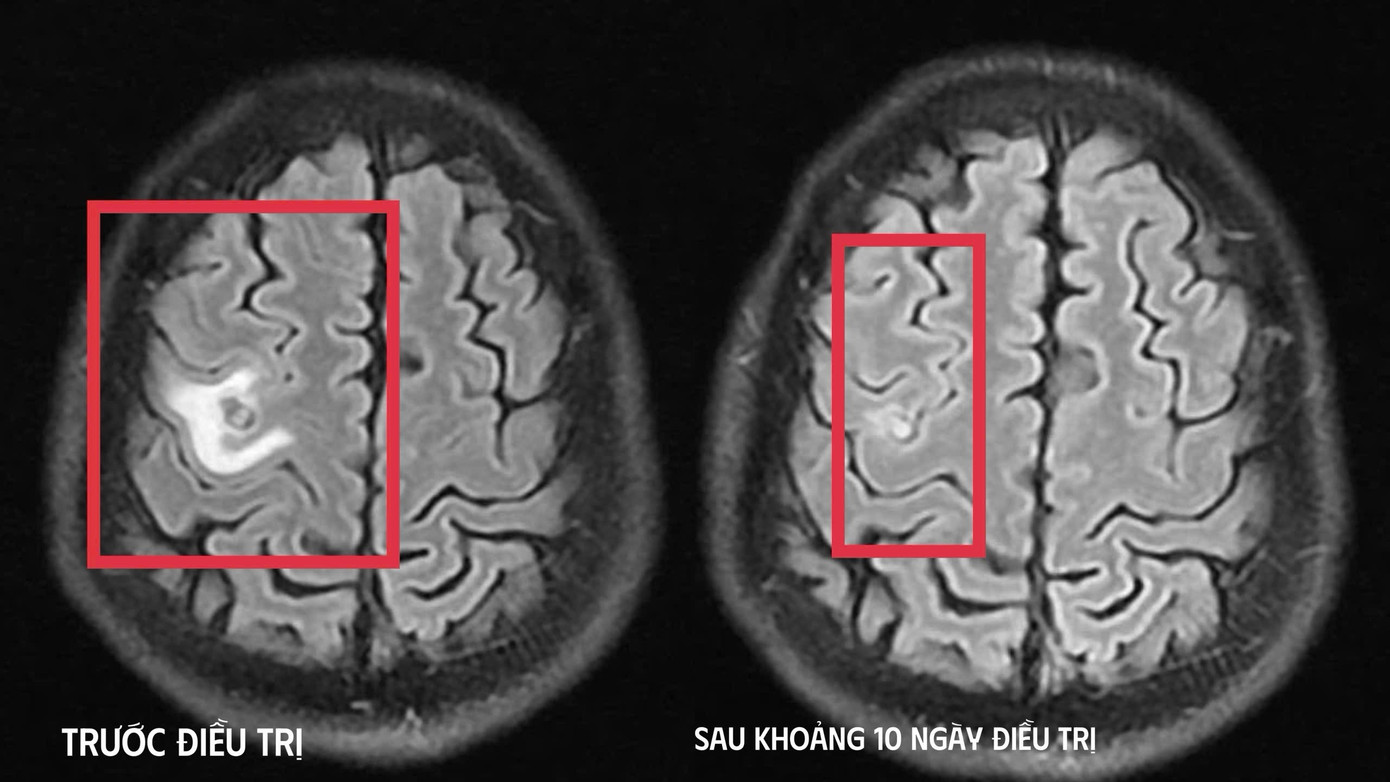

Ổ sán trước và sau điều trị trong não bệnh nhân.

Kết quả chụp cộng hưởng từ (MRI) sọ não cho thấy một tổn thương dạng nang nhỏ tại thùy trán trái, kích thước khoảng 11 x 7 mm, xung quanh có phù não nhẹ. Hình ảnh này gợi ý nhiều đến tổn thương do kí sinh trùng hơn là u não nguyên phát. Các xét nghiệm huyết thanh học tiếp tục được chỉ định, trong đó xét nghiệm kháng thể kháng sán dây chó cho kết quả dương tính, giúp khẳng định chẩn đoán tổn thương não do kí sinh trùng.

Sau khi xác định nguyên nhân, bệnh nhân được điều trị nội khoa theo phác đồ, kết hợp kiểm soát triệu chứng và theo dõi chặt chẽ diễn biến thần kinh. Sau khoảng 10 ngày điều trị nội trú, tình trạng người bệnh cải thiện rõ rệt, không còn co giật, hết tê tay, không đau đầu hay chóng mặt, toàn trạng ổn định và được cho ra viện, tiếp tục điều trị ngoại trú đủ liệu trình kéo dài 4 tuần.

Khi tái khám gần một tháng sau, kết quả chụp MRI cho thấy tổn thương não thu nhỏ rõ rệt, phù não giảm, không còn dấu hiệu tiến triển, đáp ứng điều trị tốt. Bệnh nhân được chỉ định thêm một đợt thuốc củng cố và theo dõi lâu dài.